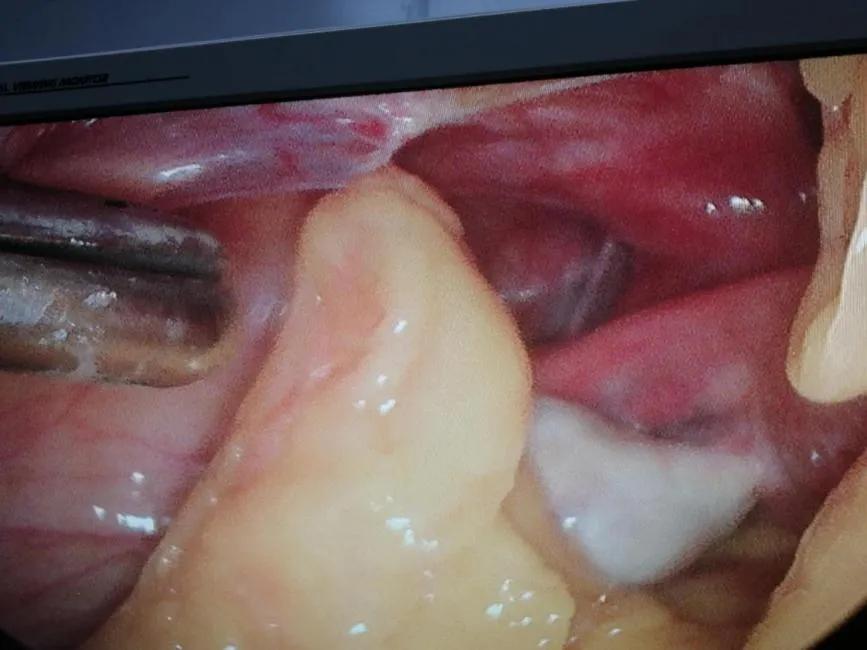

患者手术指征明确,于2020年2月18日在全麻下行腹腔镜探查。术中见:肠管、大网与腹前壁广泛致密粘连,仅脐周及两侧盆壁少量间隙,盆腔封闭。术中诊断:双侧输卵管卵巢积脓、盆腔脓肿、肠粘连、盆腔粘连。

广泛粘连的盆腔时间一分一秒的过去,手术也在有条不紊的进行。术中伴随着患者盆腔内脓肿的分离,标本取出,患者的盆腔“庐山真面目”逐渐的显露出来。手术就是“刀尖上的舞蹈”,不能有一丝一毫的偏差和失误。